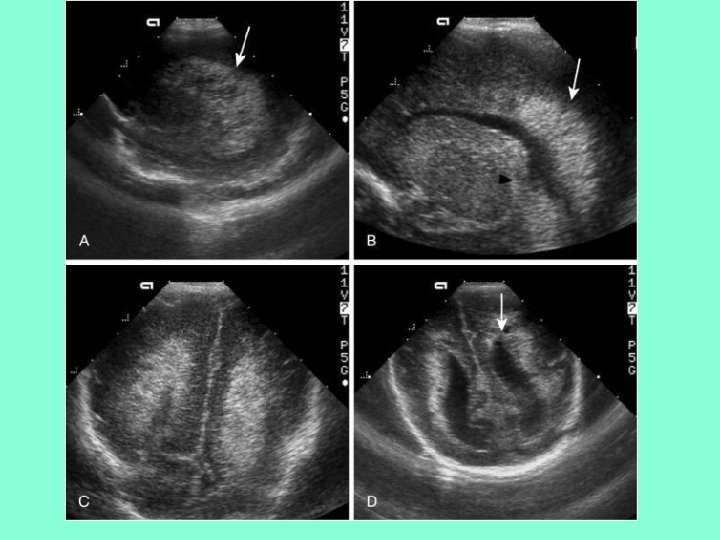

С-м Дэнди-Уокера. Агенезия червя(черная стрелочка А) с увеличением задней черепной ямки, подъем тенториума (жирная стрелочка В) и гидроцефалия (тонкая стрелочка В)

Классификация ПВЛМ From De. Vries L et al: The spectrum of leukomalacia using cranial ultrasound. Behav Brain Res 49: 1, 1992. • 1 степень – транзиторное перивентрикулярное увеличение эхоплотности в первые 7 дней жизни • 2 степени –локальные лобно-височные кисты • 3 степени - распространенные перивентрикулярные кисты • 4 степень – распространенные перивентрикулярные и субкортикальные кисты

• А – нормальный ребенок в 31 неделю ГВ • В и С - бивентрикулярные кисты